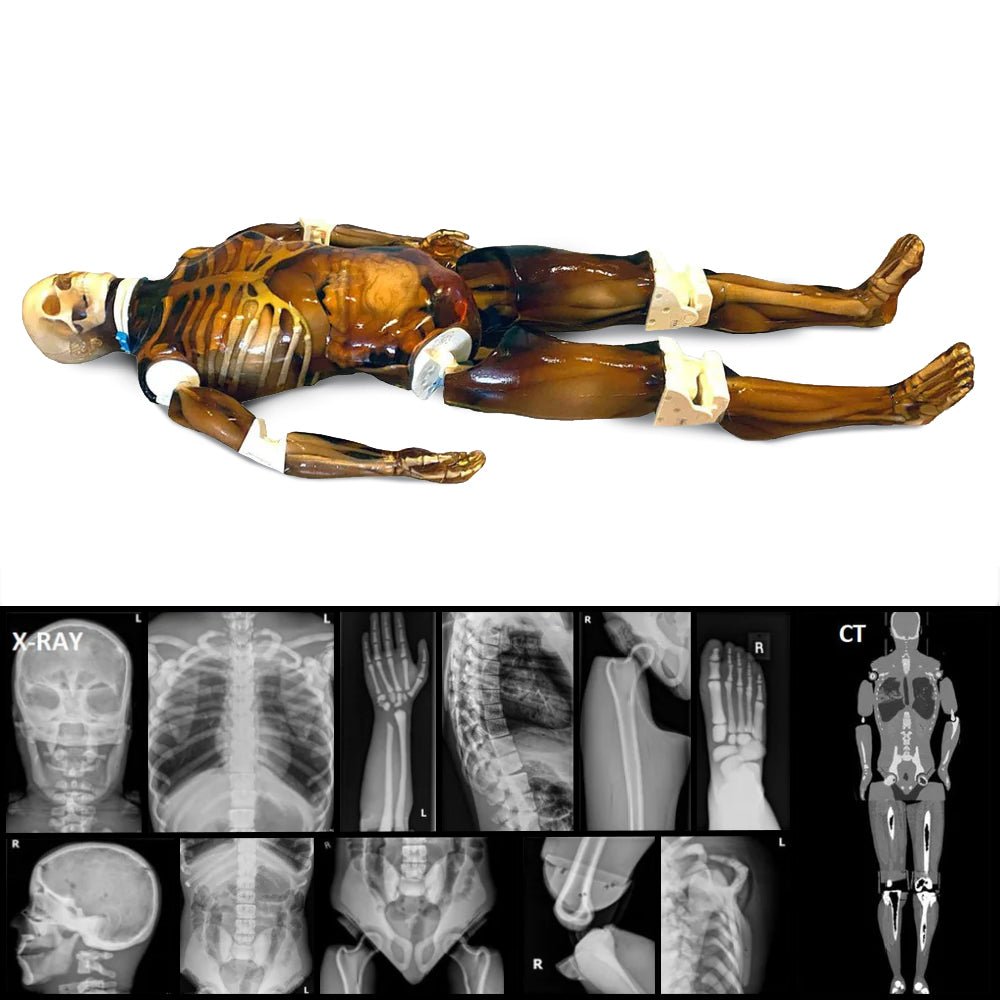

s-l1200.jpg。Amazon.com: AltSkin Adult/Kids Full Body Stretch Fabric。True Phantom Adult Male Skull Phantom | Anatomy Warehouse。【ユニークなデザイン】このフィギュアは、筋肉質な体型と大きな羽根を持つ独特なデザインが特徴です。ファンタジーやホラーの要素を取り入れた造形は、コレクションに最適です。【高品質な素材】Skeleton Baseのフィギュアは、耐久性のある素材で作られており、長期間の展示にも耐えられます。細部にわたる塗装が施されており、リアルな質感を楽しめます。【サイズと存在感】約30cmの高さで、存在感があり、どんなコレクションにも映えるアイテムです。ディスプレイ用としても最適です。- ブランド: Skeleton Base- モデル: Phantom Glow- 色: 緑・黒- サイズ: 約30cm- 特徴: 羽根付き、筋肉質な体型ご覧いただきありがとうございます。。Ops-Core Skeleton One Hole Shroud | For ACH and Gentex TBH。レトロ レア スター・ウォーズ フィギュア 3点セット。ジュラシックパーク みんなのくじ A賞。魔法の杖。スターウォーズ sp3 ベーシックフィギュア ドロイド4種 セット。スターウォーズ フィギュア ジャンク。一番くじ ストレンジャーシングス A.H.F賞セット